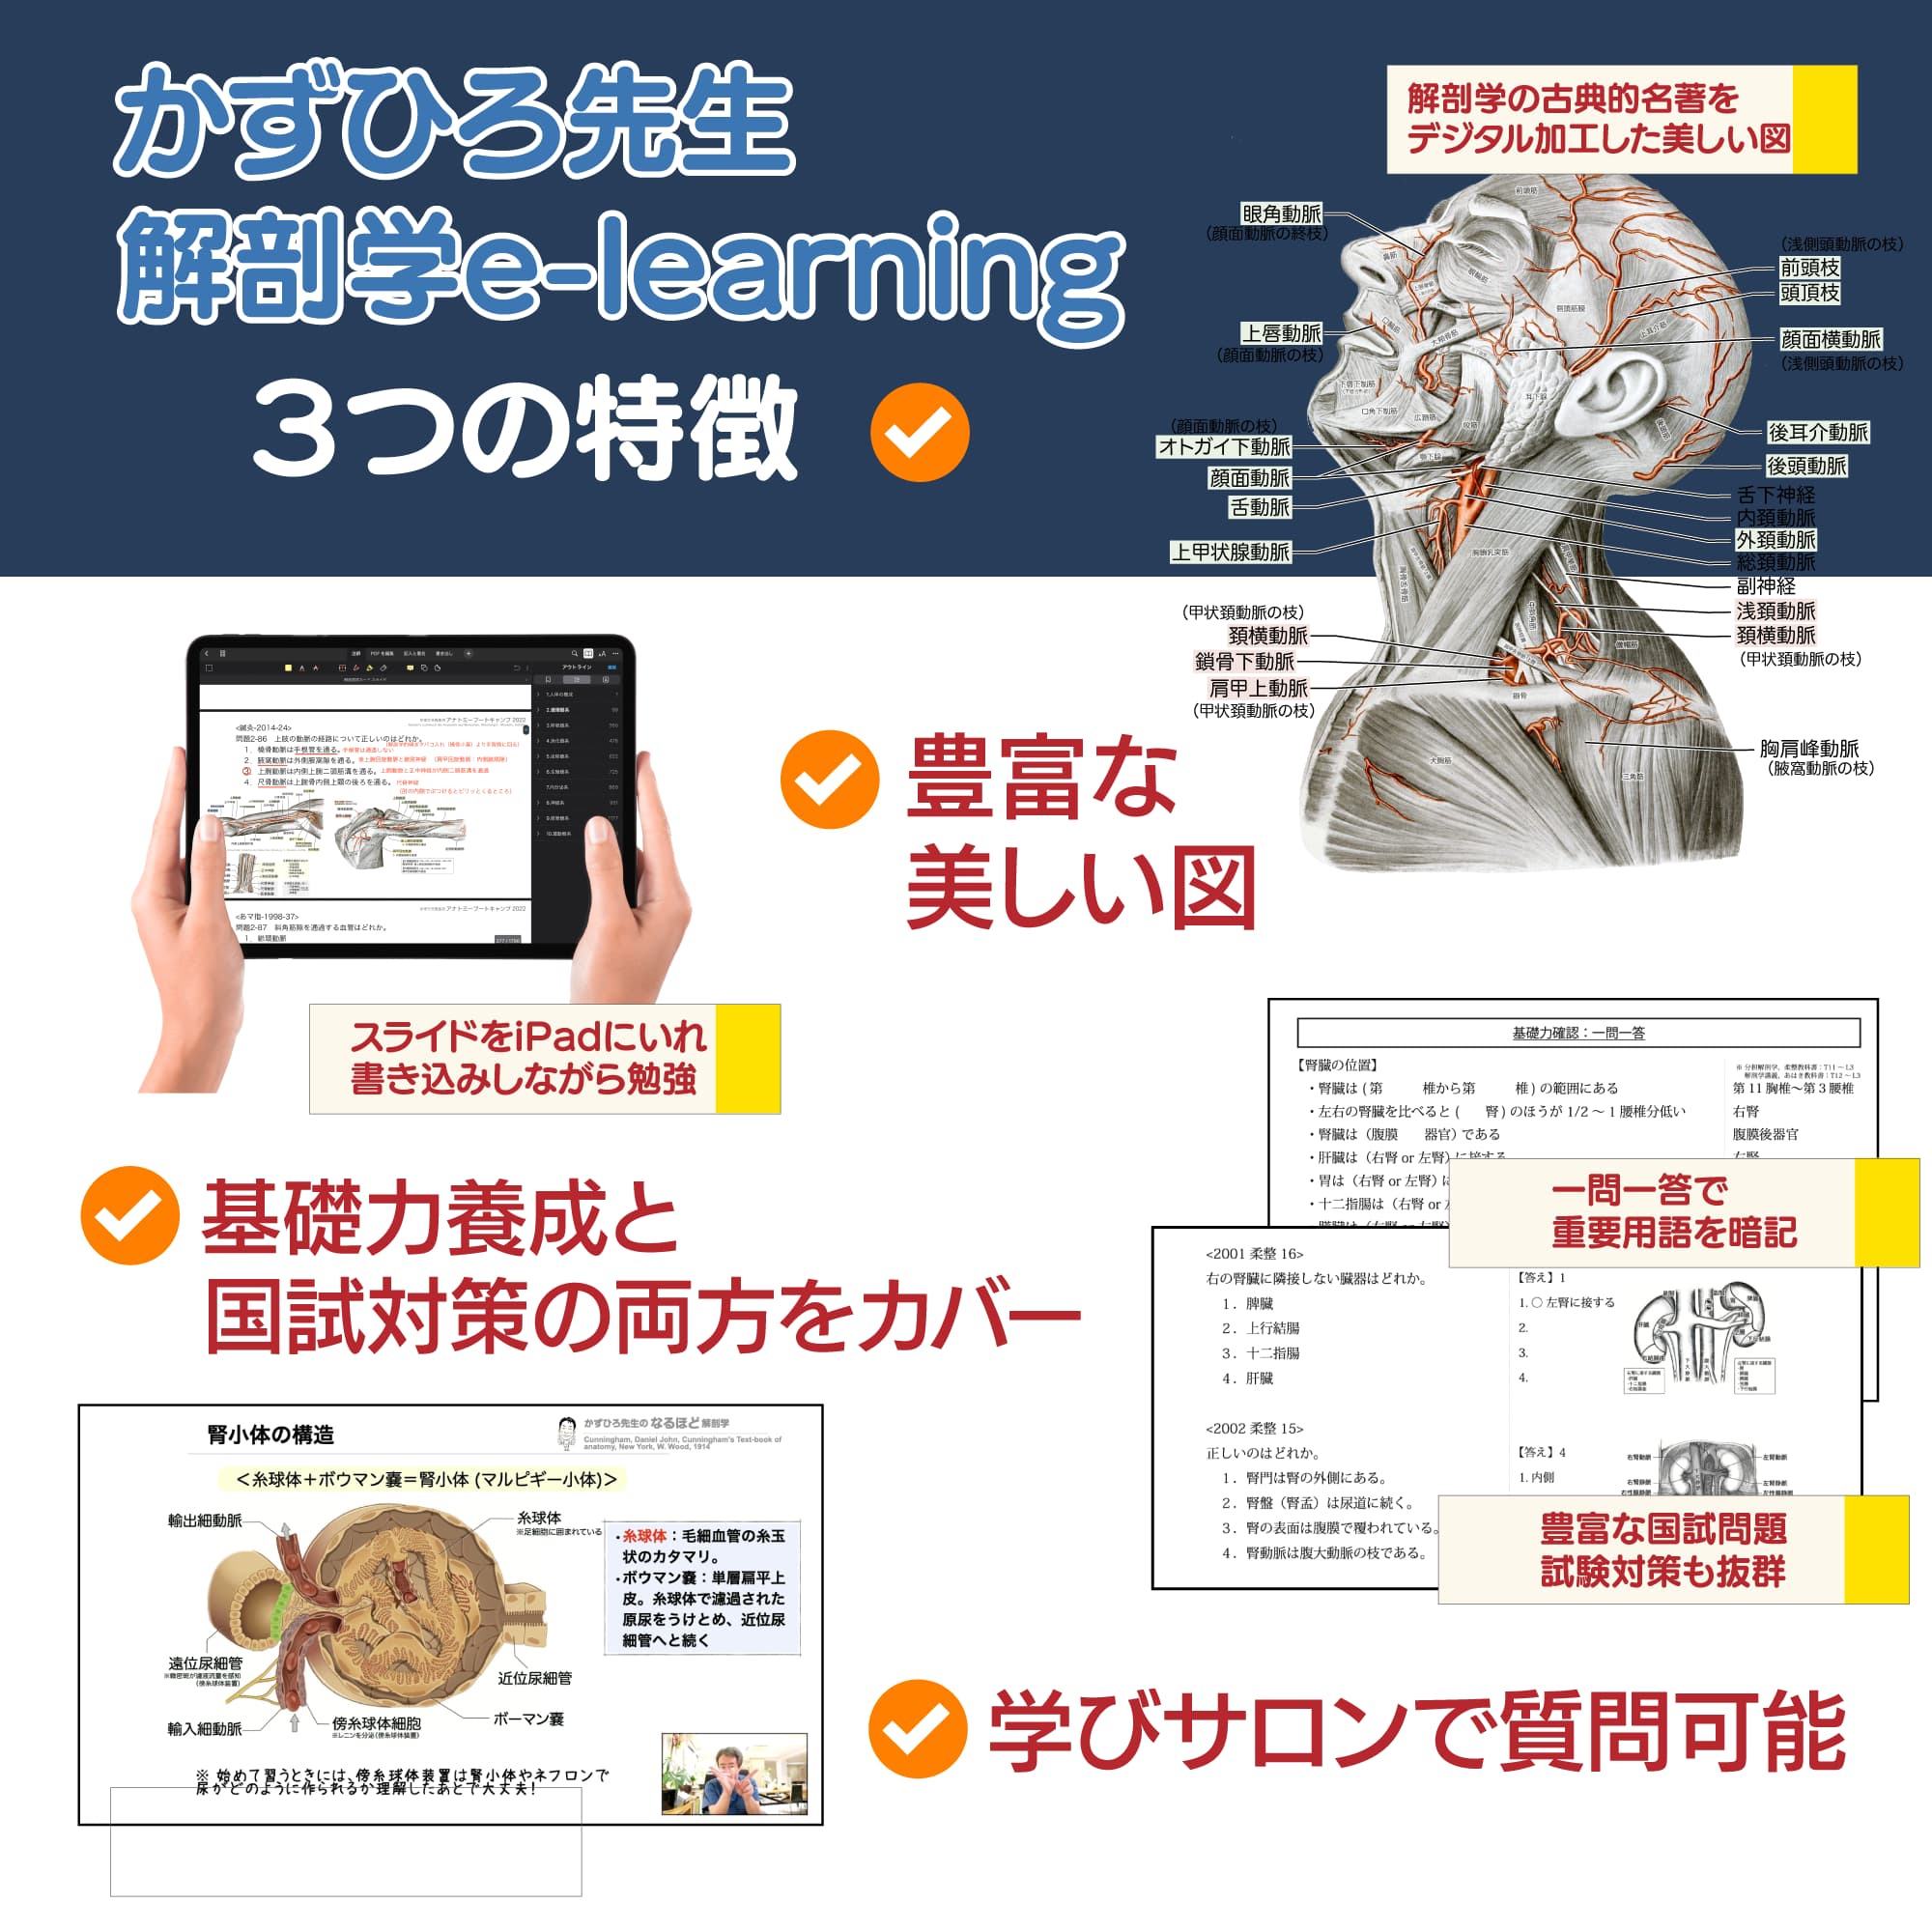

1日10回の頻度で解剖学の問題やポイントをつぶやきます。隙間時間の学習にお役立ていただければ幸いです。

Instagramでは主に医療系勉強アカをフォロー・応援させていただいています。また画像を用いた新作の資料を公開します。

Facebook 【解剖学国家試験対策】Anatomy Tokyo

Facebookでは、より細かなフォローアップや、資料の配付をしていきます。いいね!していただけると最新記事を購読できます。